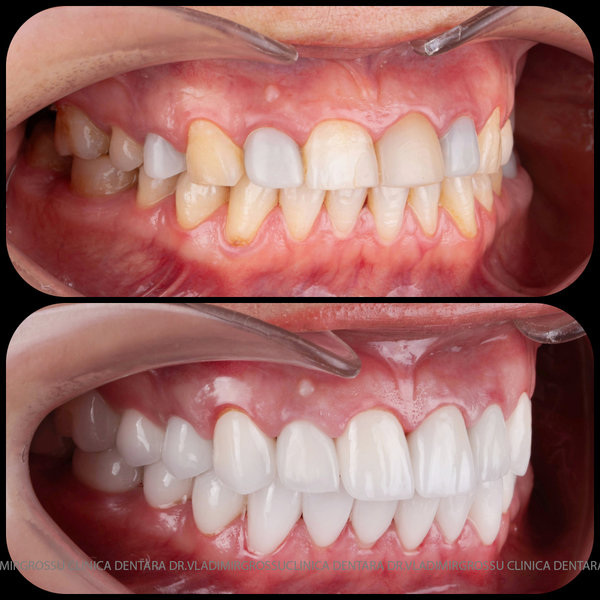

Transformările estetice și impactul reabilitării asupra vieții pacienților

Reabilitarea dentară produce o schimbare vizibilă și profundă în aspectul pacientului, cu efecte pozitive evidente asupra stimei de sine și a calității vieții. Mulți pacienți relatează bucuria redobândirii funcției masticatorii și dispariția complexelor legate de aspectul dentar.

Designul noului zâmbet

În cazul în care pacientul pune la dispoziție fotografii vechi, acestea sunt analizate, însă adesea reabilitarea presupune crearea unui zâmbet nou, personalizat. Pacienții adesea au preferințe clare privind forma și aspectul dinților viitorului zâmbet, iar echipa medicală depune toate eforturile pentru a le respecta dorințele. Dacă este cazul, se propune un design alternativ, explicat pe larg pacientului, care, de regulă, îl acceptă. Protocolul foto-video este indispensabil pentru realizarea unor astfel de lucrări.